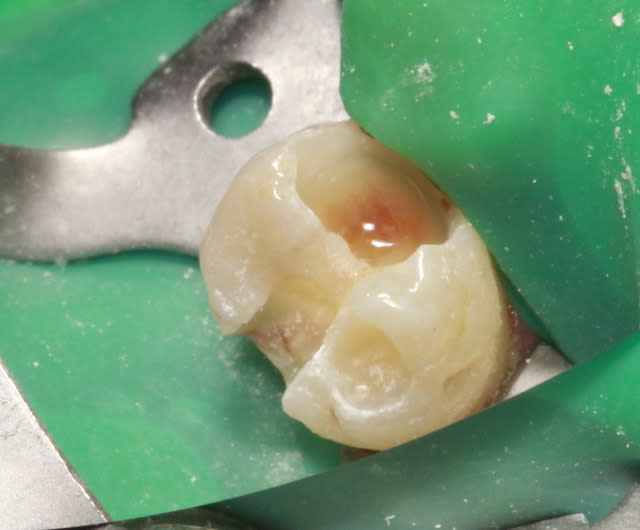

46 - fig 1,2 situation initiale

Fase du traitement: seule visite 2h

- percussion - positive

- teste du vitalité - négative

NaOCl 5% - l'irrigation et l'activation par ultrasons

chaud condensation de gutta-percha

build-up